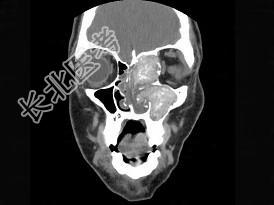

- 多项选择题17岁男性,左侧上睑下垂, CT检查如图所示,请选择正确的描述或诊断 ( )

A、左侧上颌窦、筛窦内见软组织块影

B、左侧上颌窦窦口扩大

C、鼻中隔、左侧眶内壁、上颌窦内侧壁骨质破坏

D、考虑为真菌性副鼻窦炎

E、考虑为细菌性副鼻窦炎